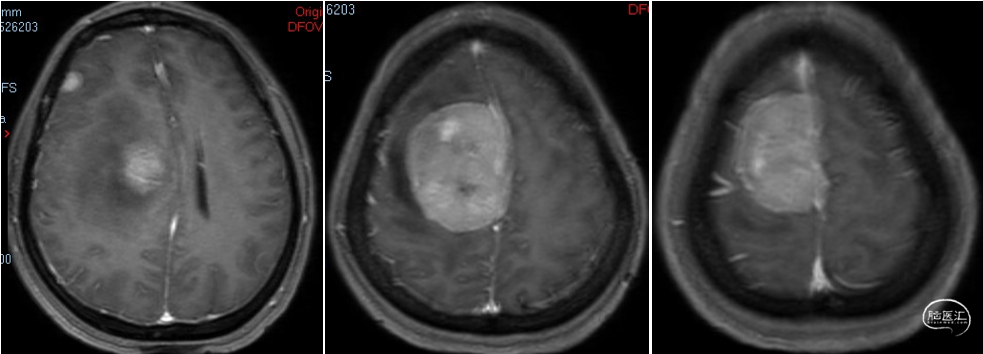

术前诊断:颅内多发脑膜瘤(右额顶部窦旁及右额部)。

术后影像